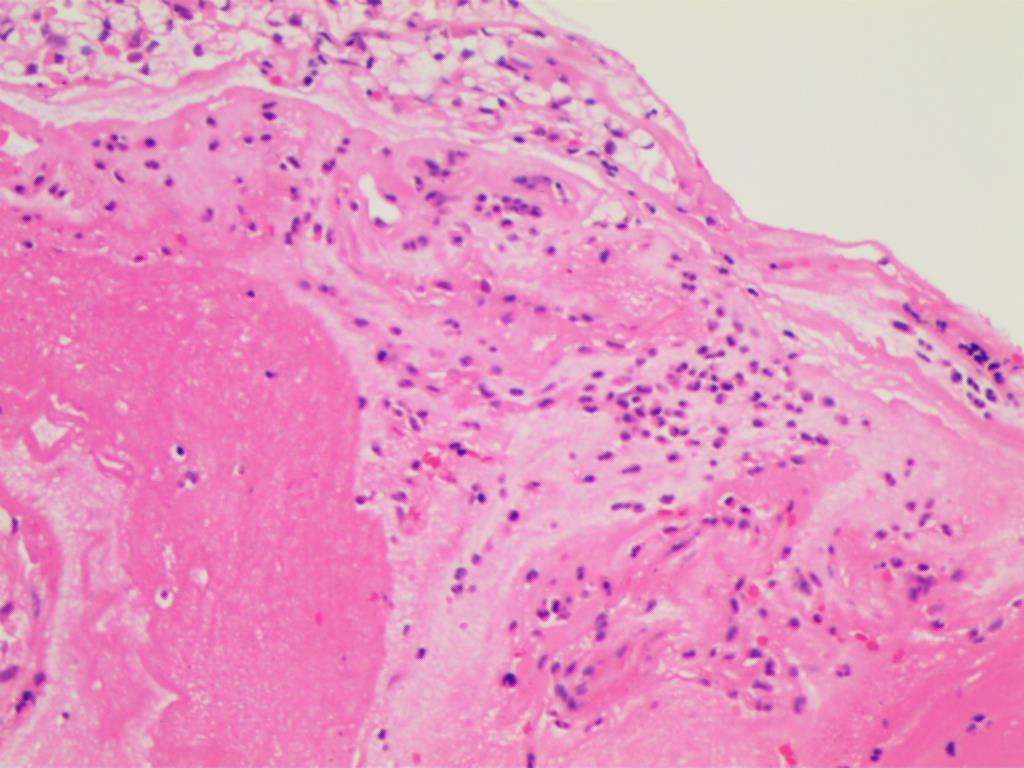

宫颈癌对于大部分女性来说也许不太陌生,它是女性的各种恶性肿瘤中,比较多见的一种,也是危害比较大的一种。

早期宫颈癌一般来说并没有特别明显的症状,但后续随着病情发展会出现阴道流血、排液等症状,晚期由于病情范围的扩张,可能会出现一些继发性症状,严重的时候可能会引起输尿管梗阻、尿毒症等情况。